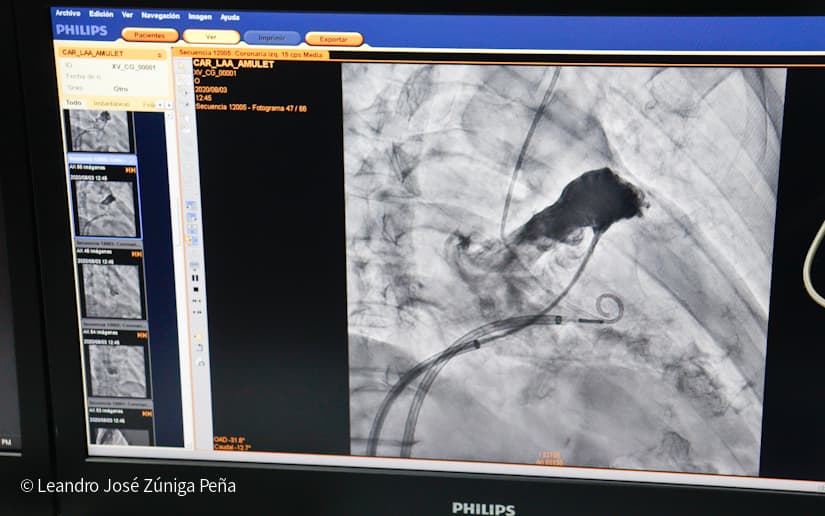

El doctor Álvaro Escalante, coordinador del área de Cardiología del Hospital Manolo Morales, indicó que este equipo permite tratar enfermedades coronarias o del corazón, arteriales periféricas, pacientes en hemodiálisis, oncológicos y con trastorno de las vías biliares.

Escalante explicó que este equipo emite rayos x de alta tecnología que permite ver el corazón y a la misma vez intervenir, de tal forma que se puede llegar a las arterias de pacientes que casi tienen un infarto, igualmente arterias obstruidas de los brazos y miembros evitando que se les amputen, así como en pacientes oncológicos la obstrucción de arterias que estén alimentando los tumores y así llevar quimioterapias, y abrir vías biliares que tengan obstrucción tumoral de la misma.

También se puede tratar las arritmias en todos aquellos pacientes que tienen palpitaciones o desmayan por x o y motivo y con este equipo se determina la causa y se tratan mediante estudio electrofisiológico y la ablación por radiofrecuencia, así como la implantación de marcapasos.